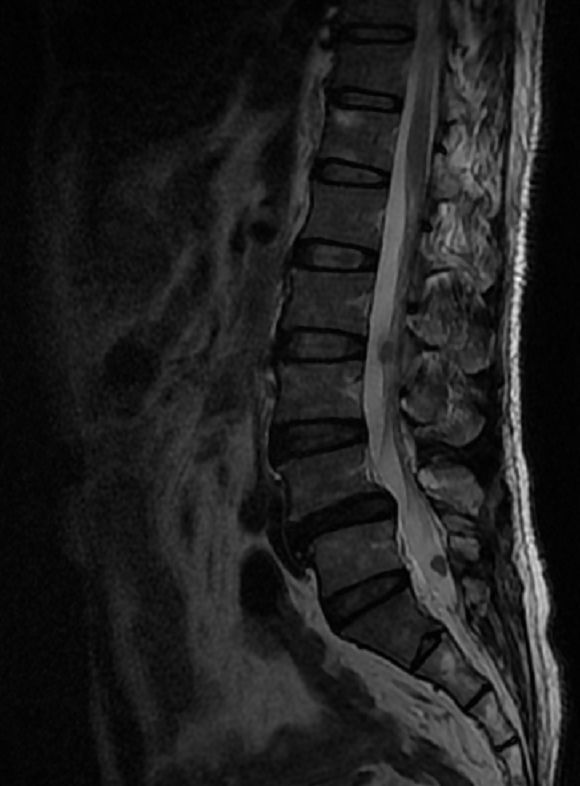

院长来看一下这个片

院长我们一开始无法辨别到底是哪种病症 但是当患者临床几天后 我们就发现

院长患者伴发多发性神经纤维瘤病 从而导致患者皮肤上有咖啡色素斑沉着及多发性小结节状肿瘤

院长所以我们最终确定它是难度最高的手术之一---神经鞘瘤

院长患者为35岁的中年人 肿瘤具体位置在椎管内 其大小为2厘米

院长只是发病原因不明确 但是排除遗传因素外 已经确定是外界的原因引发的病症

院长小宋 这种病症容错率极低 而且死亡率更是高达了20% 所以这个手术风险很高